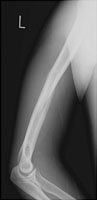

- Click on the image for a larger versionALateral radiograph of the humerus. This shows an oblique fracture of the mid humerus.